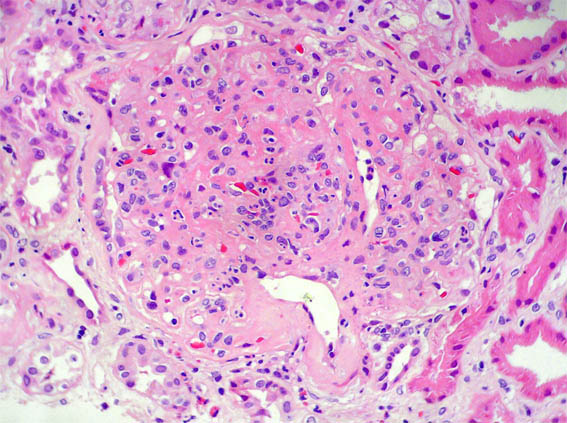

Figura 1.

H&E, X100.